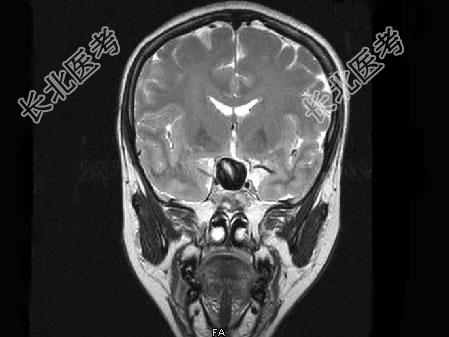

- 单项选择题女,43岁, 反复头痛10个月,CT检查如图, 最可能的诊断是 ( )